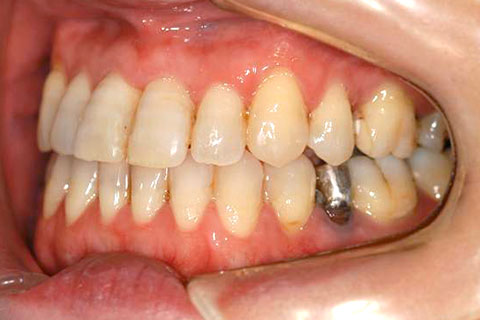

受け口(反対咬合)の症例

症例一覧